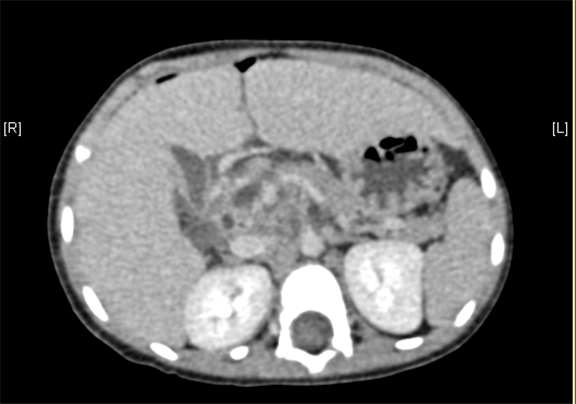

术前CT检查:

平衡期

上腹部增强CT提示肝门处占位性病变,考虑腹膜后肿瘤可能性大,畸胎瘤? AFP 11.38ng/ml